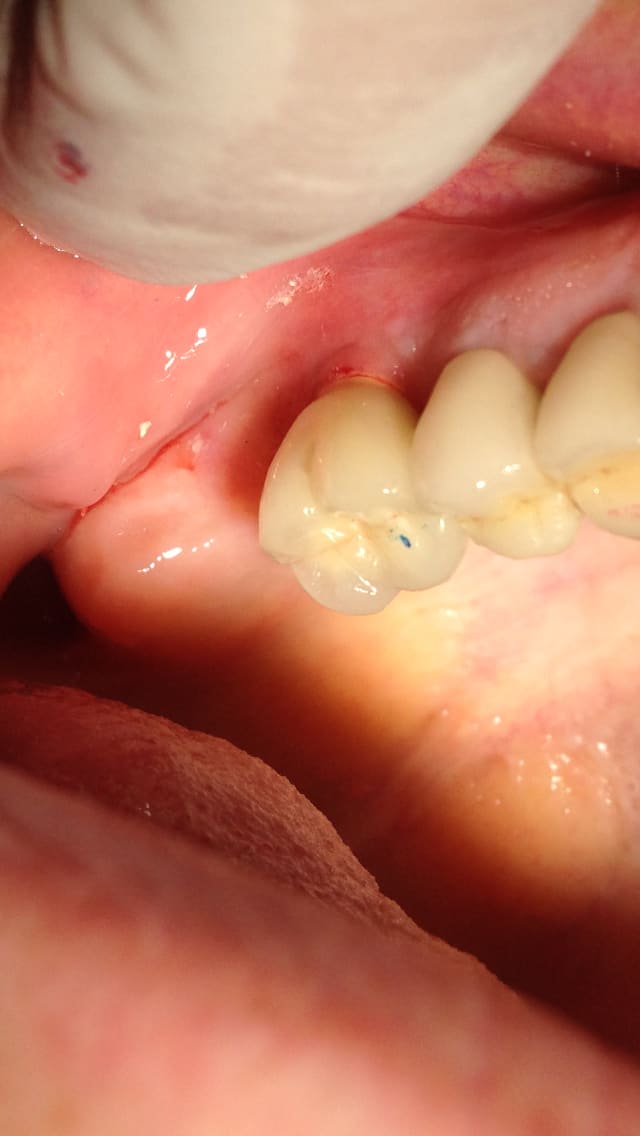

Enlaye ??? C'est le fameux que je t'avais déjà montré . J'ai repris des photos avec mon phone.... Qui c'est qui disait qu'il ne pouvait pas fermer comme ça ? Rappelle moi voir son nom 😊. On fait moins le malin tout d'un coup ! Alors on sait plus quoi dire ? 😊

Ce que je comprends pas c'est pourquoi En 25 ans ses PM n'ont pas cherché le contact avec celles du bas . Il y a juste des contacts au niveau des 7 et des incisives

non jamais d'ortho !

Bin écoute là c'est certain il a toujours fermé comme ça. "Ça a toujours été comme ça , et je mange que sur mes dernières dents " m'a t il dit

-> il ne s'est pas plaint de quoique ce soit, je lui ai parlé du redressage de chicot qui pourrait améliorer la situation. Ça n'a pas l'air de lui parler. Donc je ne vais pas perdre mon temps à lui faire des empreintes 😊

sur les 3 photos ,il y a 3 fermetures différentes .

donc celà confirme ce que je disais .